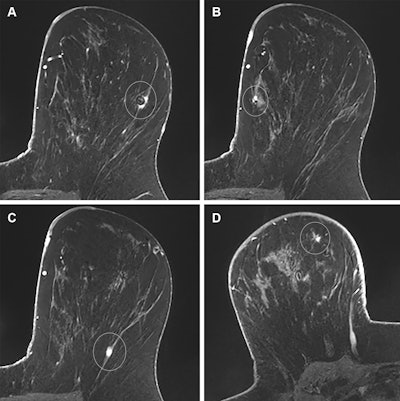

Images in a 39-year-old woman with a remote history of right breast cancer and a new diagnosis of multicentric left breast cancer; this case illustrates appropriate auditing of true- and false-positive results. (A) Axial T1-weighted postcontrast image from preoperative breast MRI shows a small invasive mammary carcinoma with biopsy clip susceptibility artifact (circle) in the lateral left breast that was diagnosed before MRI. (B) Axial T1-weighted postcontrast image from the same examination reveals a smaller invasive mammary carcinoma with biopsy clip susceptibility artifact (circle) in the medial left breast that was also diagnosed before MRI. For the purpose of auditing in this study, the larger of these two malignancies was considered the index malignancy. (C) Axial T1-weighted postcontrast image from the same examination demonstrates an additional small mass in the posterior aspect of the left breast (circle). It was described as suspicious, and a third focus of invasive mammary carcinoma was diagnosed at MRI-guided biopsy. This pathologic result was audited as a true-positive ipsilateral finding. (D) Axial T1-weighted postcontrast image from the same examination shows a fourth mass in the contralateral right breast (circle), which was also described as suspicious. MRI-guided biopsy yielded benign fat necrosis and stromal fibrosis, which was audited as a false-positive contralateral finding.Images in a 39-year-old woman with a remote history of right breast cancer and a new diagnosis of multicentric left breast cancer; this case illustrates appropriate auditing of true- and false-positive results. (A) Axial T1-weighted postcontrast image from preoperative breast MRI shows a small invasive mammary carcinoma with biopsy clip susceptibility artifact (circle) in the lateral left breast that was diagnosed before MRI. (B) Axial T1-weighted postcontrast image from the same examination reveals a smaller invasive mammary carcinoma with biopsy clip susceptibility artifact (circle) in the medial left breast that was also diagnosed before MRI. For the purpose of auditing in this study, the larger of these two malignancies was considered the index malignancy. (C) Axial T1-weighted postcontrast image from the same examination demonstrates an additional small mass in the posterior aspect of the left breast (circle). It was described as suspicious, and a third focus of invasive mammary carcinoma was diagnosed at MRI-guided biopsy. This pathologic result was audited as a true-positive ipsilateral finding. (D) Axial T1-weighted postcontrast image from the same examination shows a fourth mass in the contralateral right breast (circle), which was also described as suspicious. MRI-guided biopsy yielded benign fat necrosis and stromal fibrosis, which was audited as a false-positive contralateral finding.RSNA